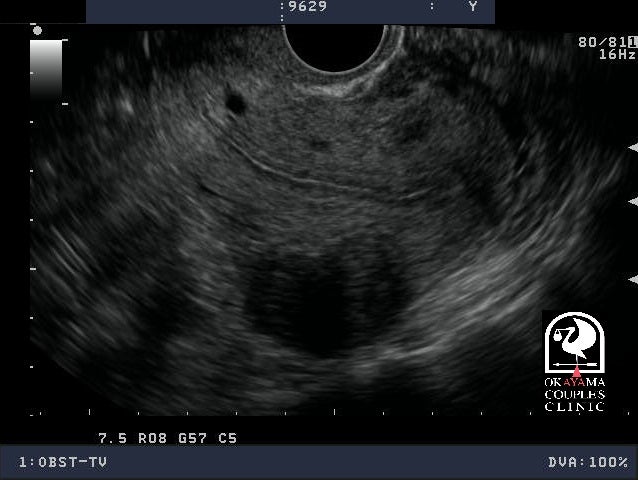

자궁근종의 진단은 일반적으로 초음파 검사를 통해 이루어집니다. 초음파는 비침습적인 안전한 방법으로, 자궁 근종의 수, 크기 및 위치를 확인할 수 있습니다. 경우에 따라, MRI나 CT 스캔을 통해 더 자세한 정보를 얻을 수 있습니다. 진단 후, 자궁근종 증상과 환자의 건강 상태를 고려하여 적절한 치료 방법을 결정합니다.